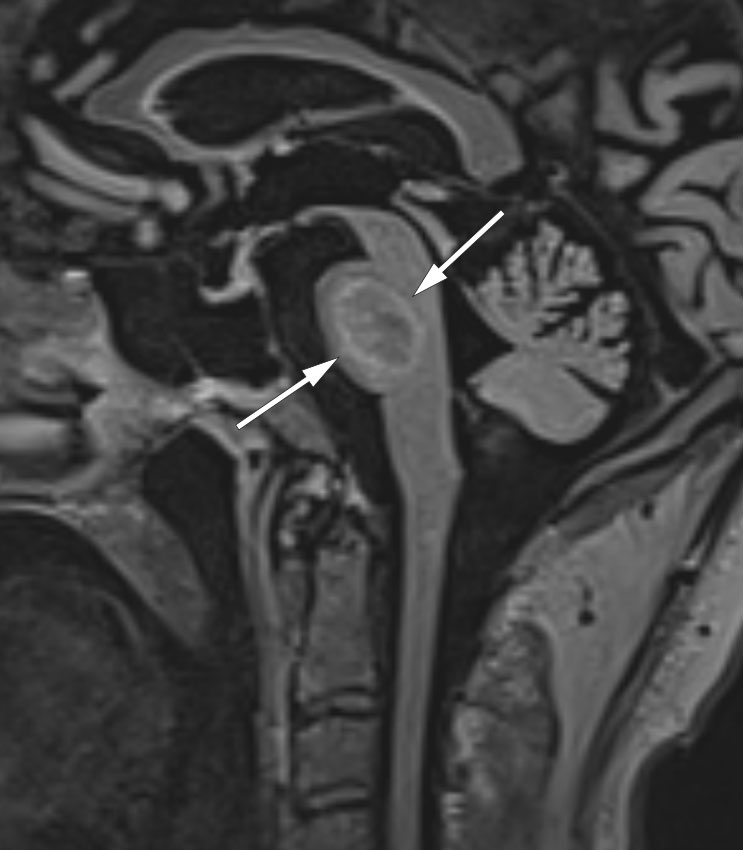

MR-bildet (sagittal FLAIR) viser et patologisk område sentralt i pons, avgrenset av en perifer brem med høyt signal. Sammenholdt med sykehistorie, kliniske funn og blodprøver var forandringene forenlige med osmotisk demyelinisering.

MR-undersøkelse viste en stor lesjon i pons med lavt T2/FLAIR signal sentralt omgitt av en perifer brem med høyt signal. På T1 sekvens viste lesjonen oppladning av kontrast perifert. Funnet var, i lys av sykdomstegn og anamnese, forenlig med osmotisk demyelinisering, også kjent som sentral pontin myelinolyse eller osmotisk demyeliniseringssyndrom – en akutt demyeliniseringslidelse som oftest skyldes for rask korrigering av hyponatremi (1). Andre risikofaktorer er hypokalemi, dårlig ernæring, alkoholoverforbruk og rask korrigering av øvrige elektrolyttforstyrrelser (1). Pasienten hadde ikke hyponatremi, men de andre ovennevnte risikofaktorene.

Osmotisk demyelinisering i pons har et typisk funn på MR-bilder, men andre differensialdiagnoser som infarkt og ponstumor bør også vurderes.